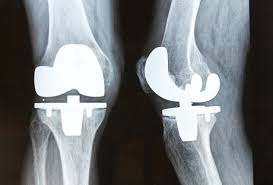

Since my wife's bones were good he was able to install the bottom section with the kind that has 2 pegs down into the lower bone and glue it in place. The bone then grows around this device. Then hopefully 20 years later we have to replace this device for a new and improved version. However, if you don't keep light enough in weight it could only last 10 years.

Here are the types of parts installed in knee replacements from Google Images: